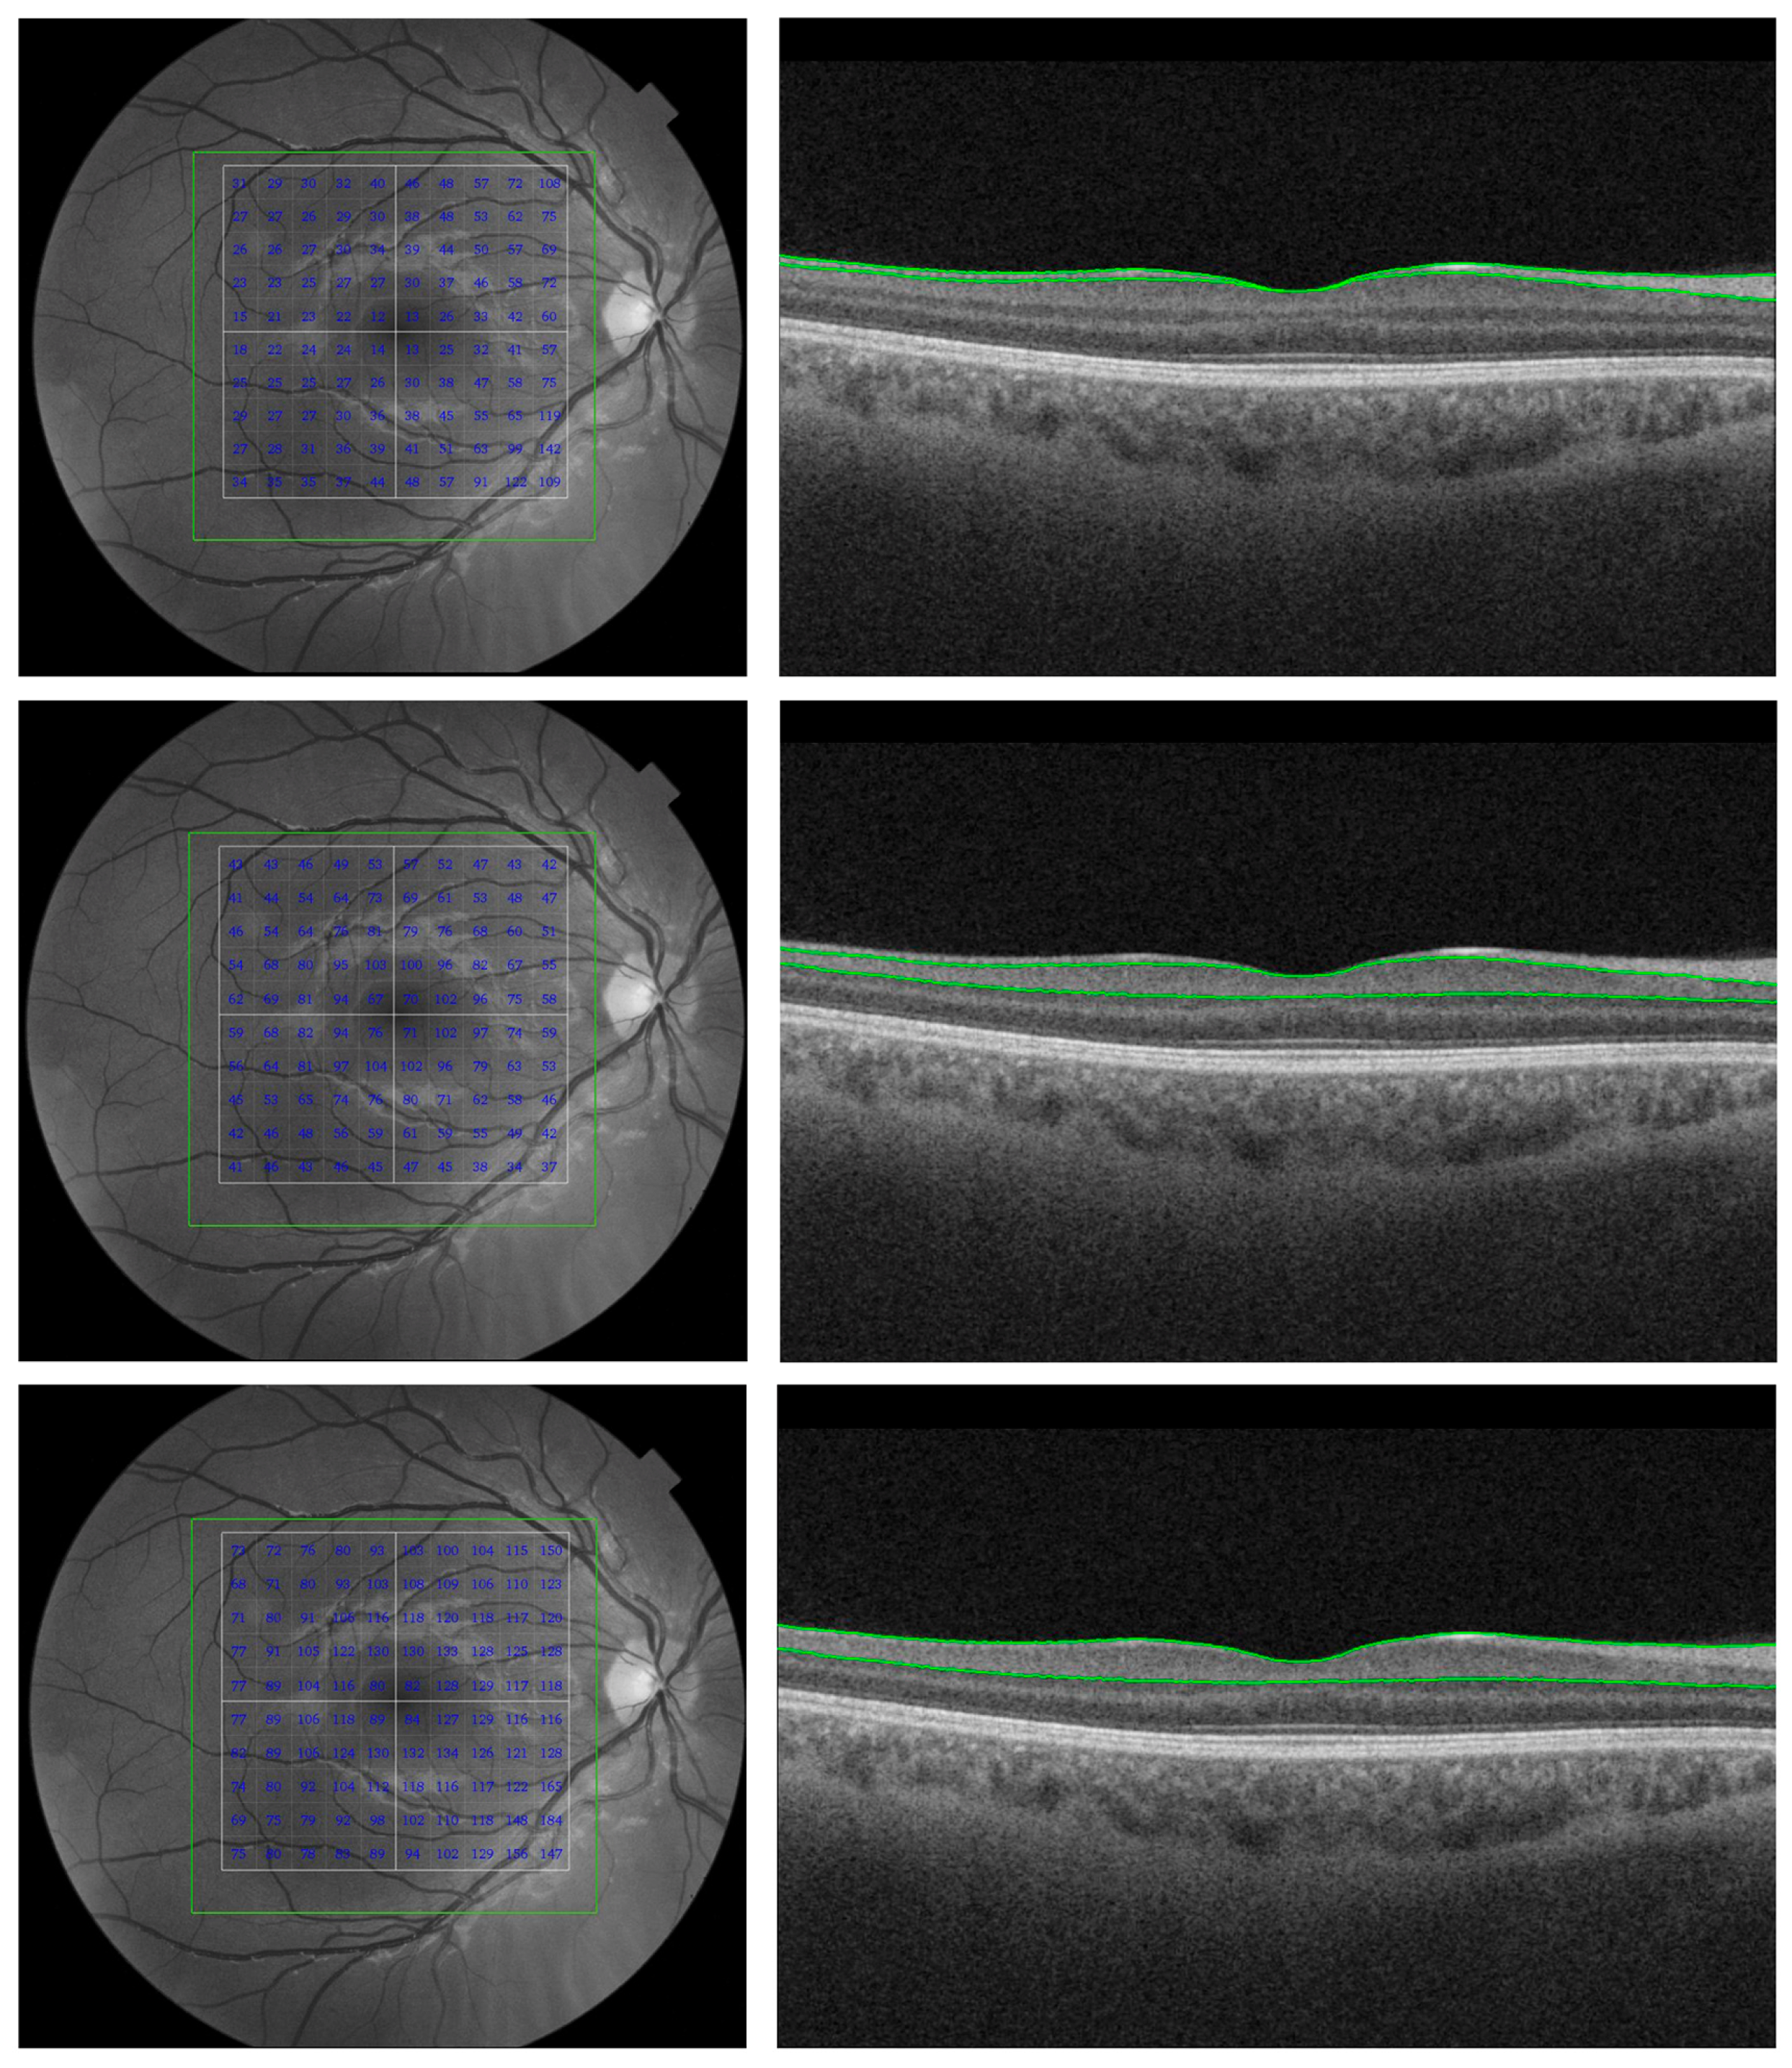

- Cunha, L.P.; Lopes, L.C.; Costa-Cunha, L.V.F.; Costa, C.F.; Pires, L.A.; Almeida, A.L.M.; Monteiro, M.L.R. Macular thickness measurements with frequency domain-OCT for quantification of retinal neural loss and its correlation with cognitive impairment in Alzheimer’s disease. PLoS ONE 2016, 11, e0153830. [Google Scholar] [CrossRef]

- Santos, C.Y.; Johnson, L.N.; Sinoff, S.E.; Festa, E.K.; Heindel, W.C.; Snyder, P.J. Change in retinal structural anatomy during the preclinical stage of Alzheimer’s disease. Alzheimers Dement. 2018, 10, 196–209. [Google Scholar] [CrossRef]

- Snyder, P.J.; Johnson, L.N.; Lim, Y.Y.; Santos, C.Y.; Alber, J.; Maruff, P.; Fernández, B. Nonvascular retinal imaging markers of preclinical Alzheimer’s disease. Alzheimers Dement. 2016, 4, 169–178. [Google Scholar] [CrossRef] [PubMed]